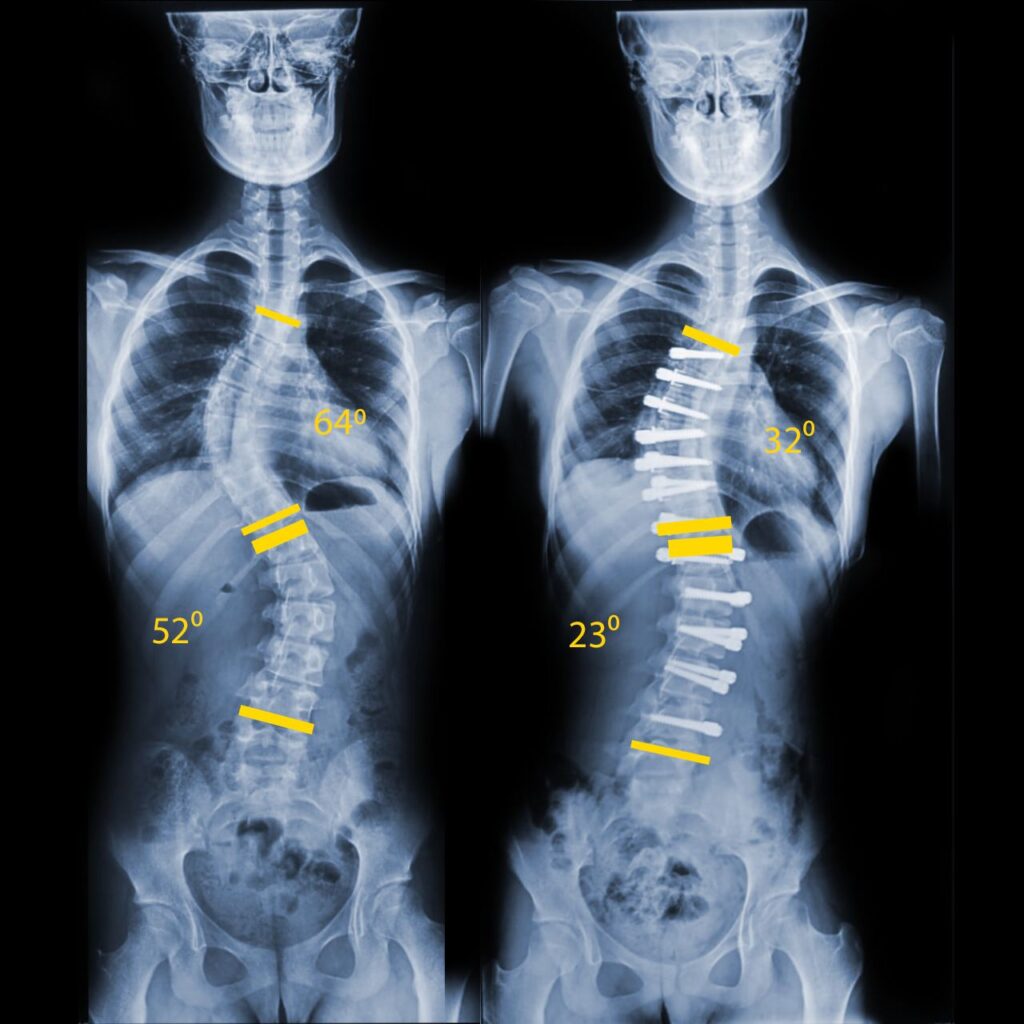

Детский сколиоз - не приговор

Сегодня хотим поделиться важной информацией: наш добрый друг-Николай Шавга,врач и ведущий специалист по коррекции сколиоза помогает детям справляться с этим непростым... Чтобы узнать, пройдите по ссылке